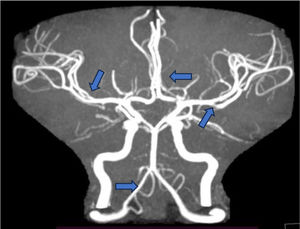

Una vez se contó con un diagnóstico clínico, se evaluó objetivamente el compromiso orgánico, para lo que se llevó a cabo una angiorresonancia cerebral, la cual reportó vasculitis de arterias cerebrales anteriores y medias bilaterales, además de disminución de calibre de arteria vertebral derecha, compatible también con vasculitis a este nivel (fig. 1). Se tomó una biopsia renal con reporte histopatológico de nefritis lúpica clase IV difusa global y se hicieron los siguientes hallazgos: presencia de más de 10 glomérulos en microscopia de luz; hallazgos glomerulares de glomerulomegalia ++, hiperplasia mesangial +, ensanchamiento mesangial +, membranas basales capilares con dobles contornos +++, adherencias capilares o sinequias +, sin fibrosis periglomerular ni proyecciones espiculares; índice de actividad, 6/24, dado por depósitos subendoteliales +, hipercelularidad endocapilar +++, exudado inflamatorio neutrofílico o cariorexis + y nefritis intersticial + e índice de cronicidad 1/12 por esclerosis glomerular en patrón focal + con reporte de inmunofluorescencia: IgG: +; IgA: ++++; IgM: ++; C3: +++; C1q: + (patrón «full house»), por lo que se decidido iniciar inducción de la remisión con ciclofosfamida a dosis de 750mg por vía intravenosa cada 4 semanas por 6 dosis.